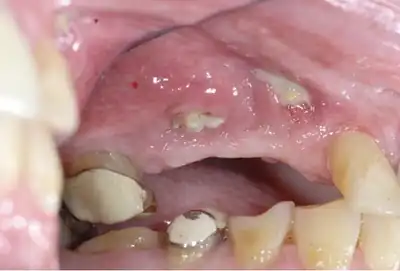

| Osteonecrosis of the jaw of the upper left jaw in a patient diagnosed with chronic venous insufficiency | |